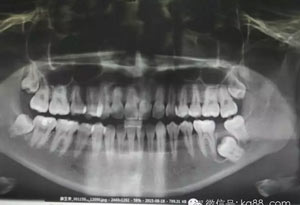

患者、薛xx、女、22歲。主訴:左側(cè)下后牙咬東西不適數(shù)年。??茩z查:37未萌出,36正常萌出,且咬合關(guān)系良好。38近中移位,輕度傾斜,48與27有咬合關(guān)系。37頰側(cè)未能捫及隆起及波動感,也未能探及盲袋。x線片檢查:37低位近中埋伏阻生,牙冠周圍有牙囊影。CBCTj檢查:牙冠周圍有囊性改變,診斷:37含牙囊腫。處理:建議手術(shù)拔除37。患者同意手術(shù)。術(shù)前簽知情同意書。

圖1.術(shù)前患者的全景片影像檢查情況:37未萌出,牙冠周圍有囊性陰影,牙根接近下頜骨皮質(zhì)骨邊緣。